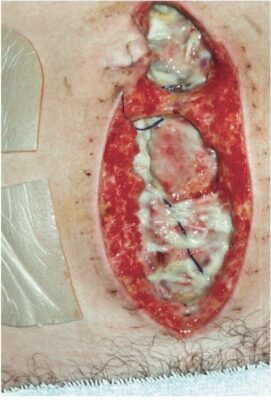

Thì đầu (Primary Intention, ý định ban đầu)

Lành vết thương thì đầu xảy ra khi nhân viên y tế đóng vết thương bằng cách kéo các mép vết thương lại sát với nhau, thông qua việc sử dụng chỉ khâu, kim ghim, keo dán, ghép da hoặc vạt da. Các vết thương được đóng lại bởi chủ ý ban đầu vẫn trải qua các giai đoạn lành vết thương nhưng thường trong một khoảng thời gian ngắn hơn. Một vết thương đã được đóng lại do chủ ý ban đầu, sau đó lại hở ra do bị rách hoặc nhiễm trùng được gọi là tách vết thương (dehiscence) (Hình). Sau khi vết thương bị tách ra, vết thương đó hầu như luôn luôn được để hở đóng lại thì hai.